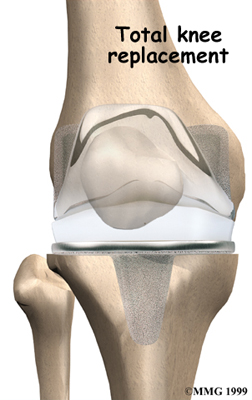

Artificial Knee Replacement

An artificial knee replacement is the ultimate solution for advanced knee OA.

Surgeons prefer not to put a new knee joint in patients younger than 60. This is because younger patients are generally more active and might put too much stress on the joint, causing it to loosen or even crack. A revision surgery to replace a damaged prosthesis is harder to do, has more possible complications, and is usually less successful than a first-time joint replacement surgery.

Related Document: FYZICAL Boulder & Horizon's Guide to Artificial Joint Replacement of the Knee